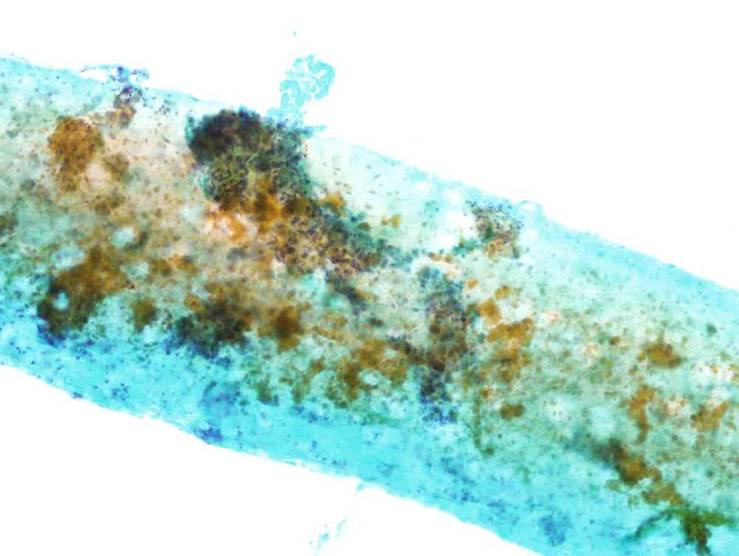

細胞診所見

病変部の穿刺吸引細胞診では,核形不整で核内封入体を有する小型細胞の集塊が散見され,甲状腺乳頭癌などとの鑑別が困難であり,組織診断を要すると結論した.

組織所見

前額部皮下から筋層にかけて,類円形で細胞境界の不明瞭な細胞が胞巣状に増殖しており,しばしば核内封入体の存在を認めた.周囲組織の破壊や壊死は認めなかった.免疫組織化学的検討を行ったところ,腫瘍細胞はTTF-1 (-), HBME-1 (-), cytokeratin 7 (-), cytokeratin 20 (-), EMA (+)であった.MIB-1 labeling indexは1%以下であった.